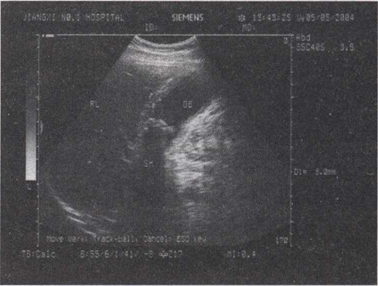

49.患者右上腹疼痛1周,厌油食,超声见胆囊内强回声,可移动,如图所示,考虑为()